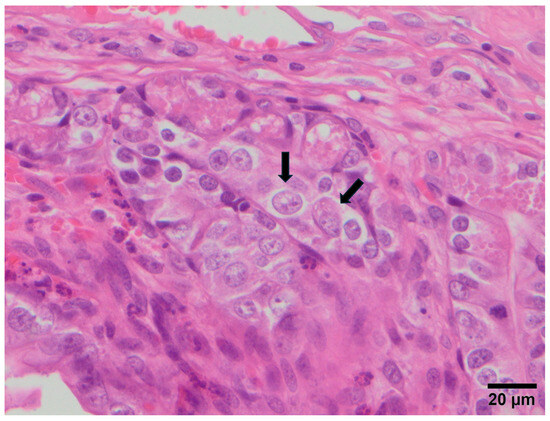

3.2. Study B: Lesional Study